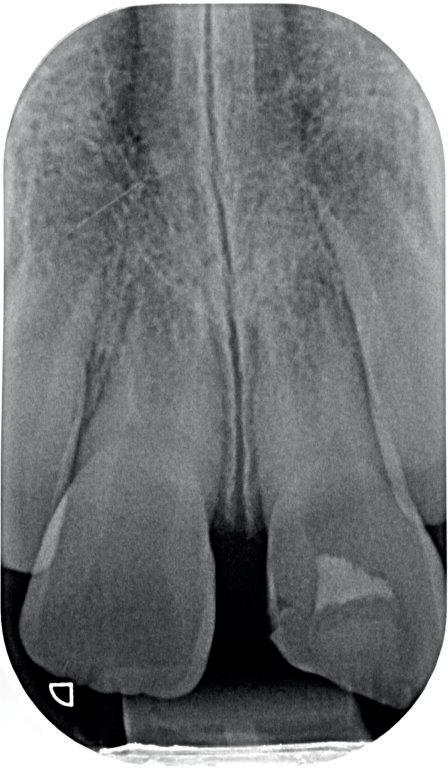

9. Situatie één week na het trauma.

10-11. Vier weken na het trauma is de TTS verwijderd en de endodontische behandeling aan element 11 voltooid. Vanwege de brede apicale diameter is er afgesloten met MTA).

12. Röntgenbeeld 3 maanden na het trauma. Met dank aan Tristan Staas.